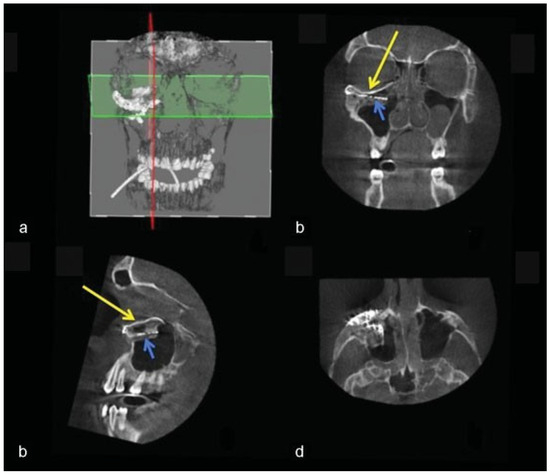

Figure 12. Case 3: Intraoperative 3D imaging using the Pulsera fluoroscopy system. (a) 3D reconstruction and section plane indication. (b) Good fit of the two puzzle pieces (long yellow arrow). Malpositioned mesh (short blue arrow). (c) Good fit of the medial puzzle-piece (long yellow arrow). The titanium mesh was not prebent and was 7 mm too low at the posterior sigmoid bulge (short blue arrow). (d) Axial view of the titanium mesh. The two-piece puzzle implants are visible only where they overlap the infraorbital rim.

A 28-year-old man was referred with disabling diplopia and severe globe malposition after two repairs of an impure orbital floor fracture using a stock titanium orbital mesh plate (►Figure 9). He had been hit by a pulley in a work accident. The presence of the previously inserted titanium mesh slightly hindered implant design because of the scatter effect on CT scan. Mirroring revealed a height difference of 7 mm between the unaffected side and the mesh on the affected side (►Figure 10, Figure 11 and Figure 12). The 3D model had to take into account the lower position of the orbital rim, and the screw position was based on the amount of remaining bone and positions of the mesh, infraorbital canal, and lacrimal system. The porous implants were printed with a double tongue-in-groove design (►Figure 1 and Figure 10). The puzzle-piece design allowed precise fit between the first and second implants (►Figure 12). Anterior flanges were not necessary as the shape of the reconstructed infraorbital rim provided anteroposterior guidance. Slight diplopia in extreme upward gaze and lagophthalmos remained because of previous fibrosis (►Figure 9).